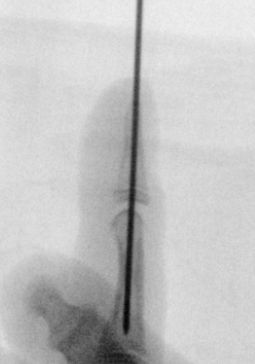

- fixerar frakturen med längsgående stift förbi DIP-led

Seymour-fraktur innan, under och efter operation - Fyseolysfraktur (Salter-Harris typ I) i distala falangen: